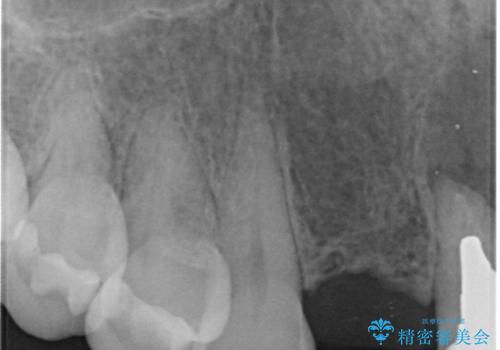

- 入れ歯での生活がストレスで他のものに変えたいとのことで来院された患者様です。

根の状態も良くなかったため、根管治療から行うこととなりました。

左上2番の歯は歯根が割れていたため抜歯し、入れ歯をブリッジに変えていきます。

- 右上1左上1:根管治療(リトリートメント)+土台(ファイバーコア)/99,000円×2本+22,000円×2本 右上123左上123:仮歯+ジルコニアクラウン(スタンダード):11,000円×6+121,000円×6 計1,034,000円(税込)費用は治療当時の料金となります